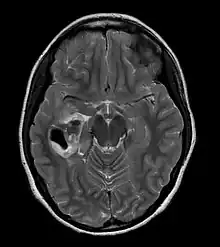

![]() | |

| CT scan of a brain with pleomorphic xanthoastrocytoma. The classic radiographic appearance is one of a superficially situated tumor, here a mural nodule, associated with an underlying cyst. |